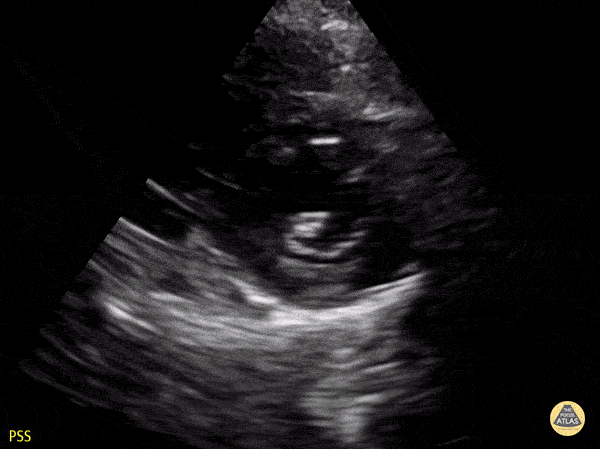

Normal PSSA apex in a 4-year-old preschooler. Contributor: Jaron Smith, MD, Phoenix Children's Hospital